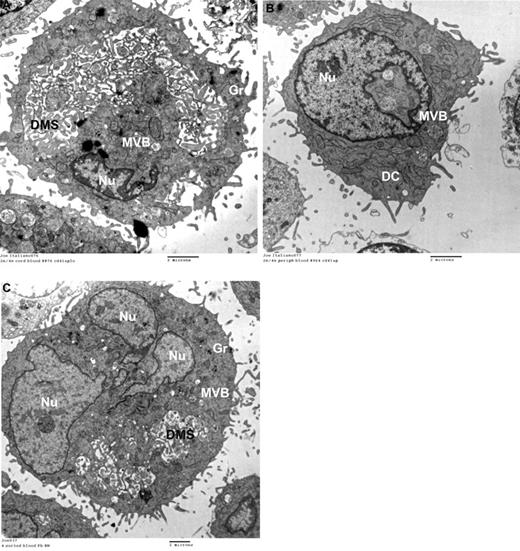

Based on the CD42b-expression patterns, we further hypothesized that neonatal 2N and 4N MKs would be more cytoplasmically mature than adult MKs of comparable ploidy. To investigate this, we flow-sorted 2N and 4N MKs generated from CB compared with PB cultures, and evaluated them by thin-section electron microscopy (n = 300 2N/4N MKs per group). Mature MKs were defined as those having an enlarged cytoplasm, abundant granules, and a well-developed DMS. Based on this definition, 58% of CB-derived 2N/4N MKs were mature (Figure 2A), compared with only 23% of 2N/4N PB-MKs (most low-ploidy PB-MKs were immature, as shown in Figure 2B). Interestingly, 54% of polyploid (≥ 8N) PB-MKs were mature, a percentage comparable with that of low-ploidy CB-MKs (Figure 2C).

Ultrastructure of MKs by transmission electron microscopy. Human MKs of different ploidy levels were flow sorted after anti-human CD41-FITC and Hoechst 33342 staining and examined by transmission electron microscopy. (A) Representative flow-sorted 2N/4N CB-MKs. The majority of these MKs were mature and exhibited abundant platelet granules and a well-developed DMS. (B) In contrast, 77% of flow-sorted 2N/4N PB-MKs were immature, as evidenced by the absence of a DMS and the paucity of granules (Gr) seen in this representative electron photomicrograph. These immature forms also exhibited multivesicular bodies (MVBs) and dense compartments (DCs), representing the precursors of platelet granules and of the DMS, respectively. (C) Fifty-four percent of all flow-sorted 8N PB-MKs were ultrastructurally similar to the mature neonatal 2N/4N MKs, although they were larger. All images were taken on a G2 Spirit BioTWIN transmission electron microscope (Tecnai) at an accelerating voltage of 80 kV, and recorded with a 2k CCD camera (Advanced Microscopy Techniques).